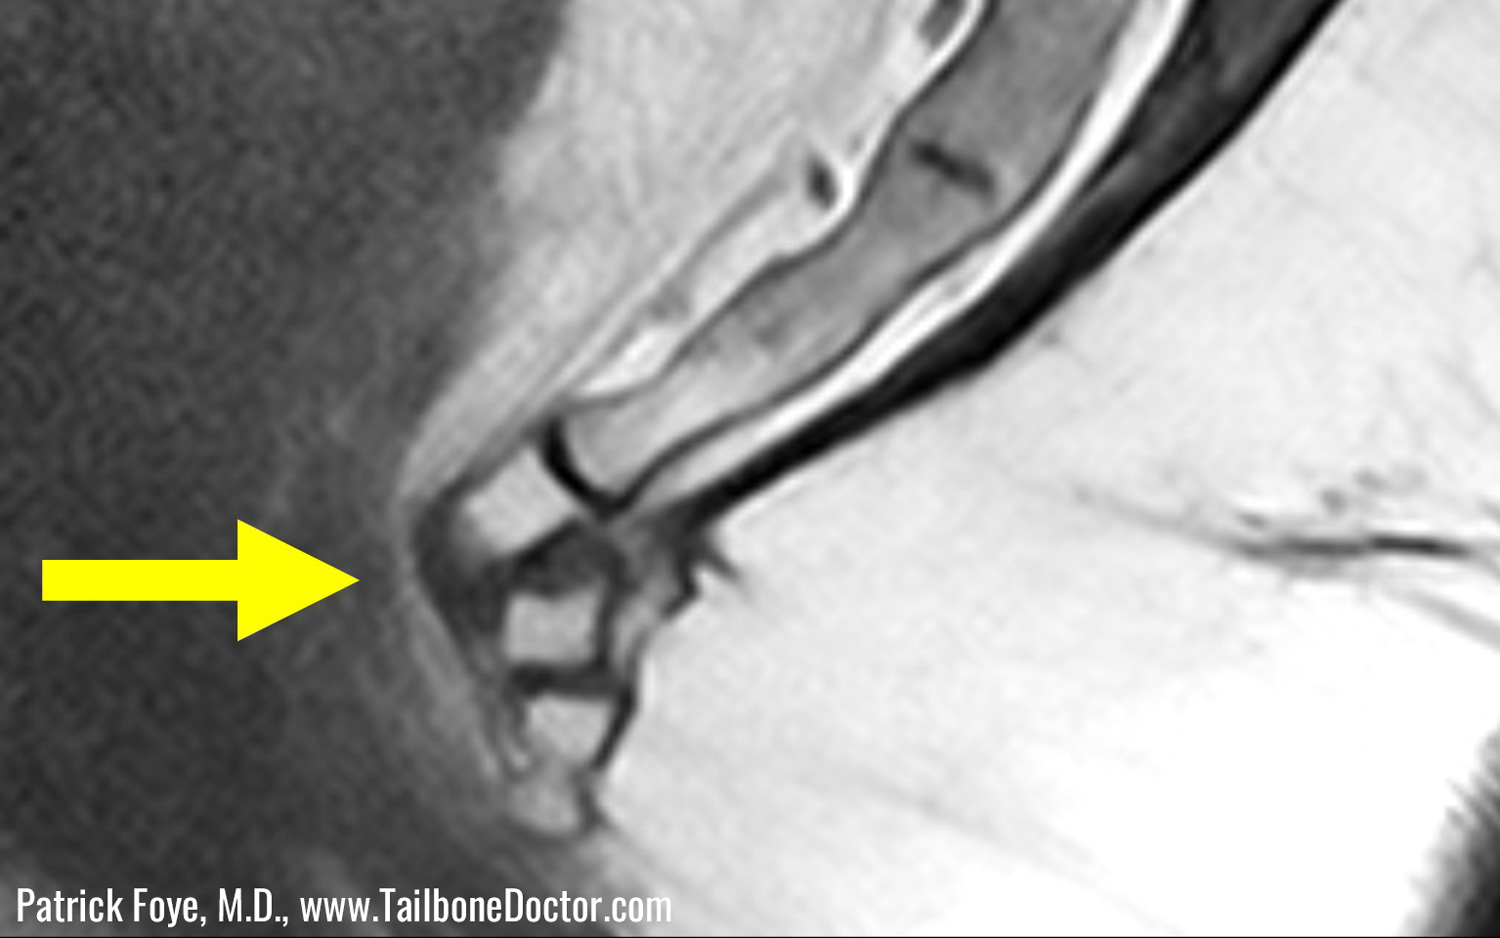

When diagnosing a tailbone injury, it's important to X-ray patients when they are sitting down, Foye said. That's because the tailbone may look normal when the person is standing, "but when they're putting their body weight onto the coccyx by sitting and leaning back, the X-rays may show a complete, 100 percent dislocation," Foye said.